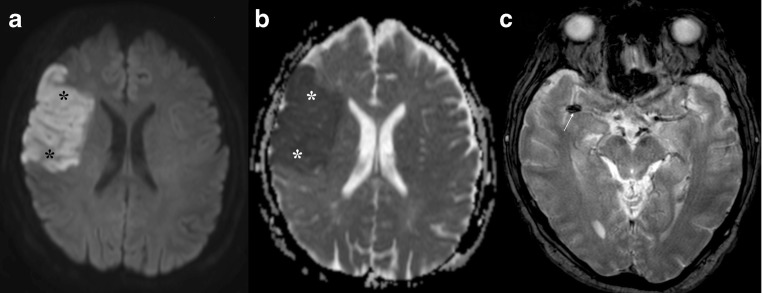

Fig. 8.

GBM. Left parieto-occipital lesion with peripheral vasogenic oedema. DWI and ADC (a and b, respectively) show a clear area of increased diffusion within the core, corresponding to a necrotic centre. On T1 3D post gadolinium the mass shows ring enhancement

Fig. 9.

Subacute haematoma. Right parietal mass (arrowhead) showing diffusion restriction within the core on DWI and ADC maps (a and b, respectively) and a ring-enhancing pattern on T1 post gadolinium (c). This was a subacute haematoma. Clinical context is important to differentiate haemorrhage from abscess. There is also a subacute ischaemic lesion in the inferior right frontal lobe (arrows) that shows early pseudonormalisation of the ADC and gyriform enhancement post gadolinium